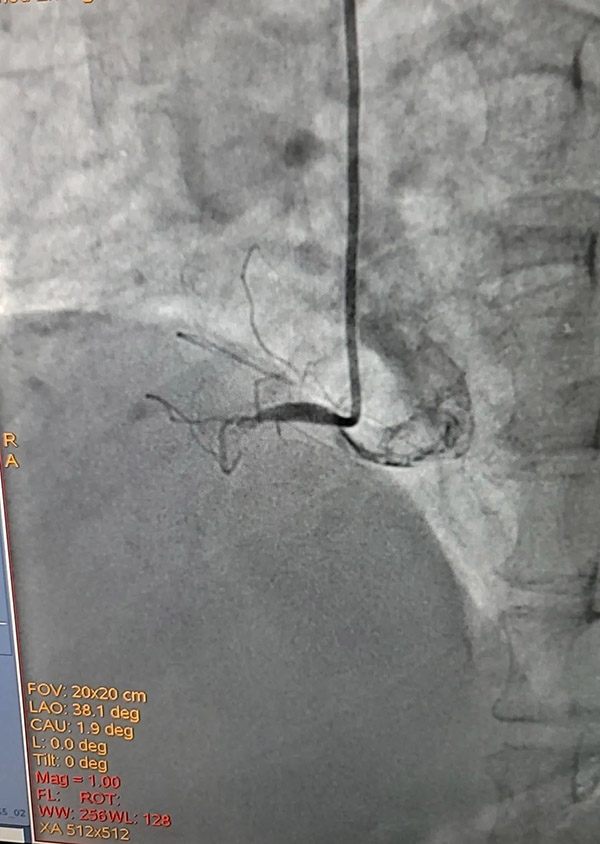

從“120”轉(zhuǎn)運(yùn)到急診科搶救、完善術(shù)前檢查,再到介入室行冠脈造影、支架植入,無(wú)縫對(duì)接,第一時(shí)間建立起患者生命急救綠色通道。全程時(shí)間不到40分鐘?;颊唔樌慕Y(jié)束手術(shù),安穩(wěn)的返回病房。

冠脈造影支架植入術(shù)后患者安返病房